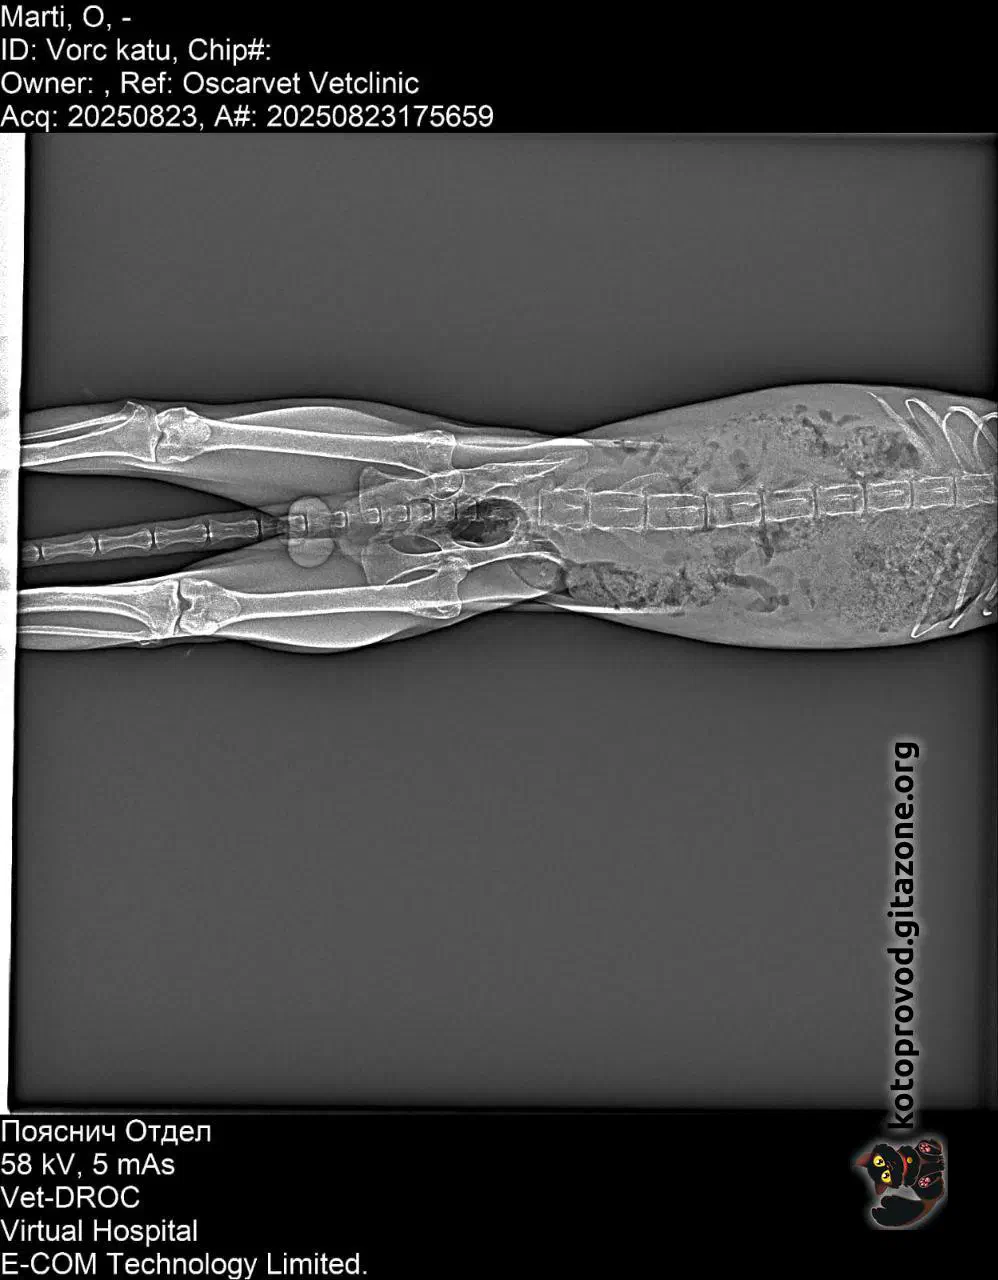

Мартини (бело-рыжий) — мальчик, возраст пока не понятен. Сдали анализы крови, сделали УЗИ — ясности с диагнозом пока нет. Есть несколько гипотез, одна хуже другой. Факты: поджелудочная, почки, печень — деформированы, нарушены структуры. Кровь по показателям намекает, что проблемы с кроветворением. Меньшее из всех его проблем — застарелая травма таза, из-за которой он с трудом передвигается. Вероятно, испытывает боль.

Рентген